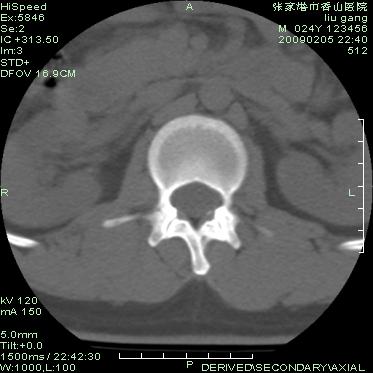

以下是引用随光逐影在2009-3-11 14:43:00的发言:[br]平片:l3、4、5及s1前上缘见类似“切角征”。[br]ct扫描:腰椎多个节段椎间盘向椎体内(椎体前部)突出。